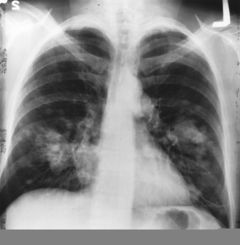

| Cross section of a human lung. The white area in the upper lobe is cancer; the black areas are discoloration due to smoking. | |